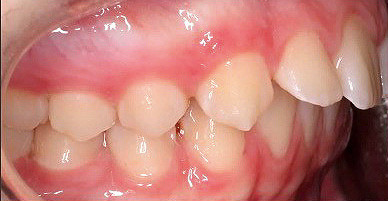

Klinisches Fallbeispiel 2 (Abb. 2a–y)

Distalbiss und tiefer Biss bei einem zwölfjährigen Mädchen. Die Behandlung erfolgte mit Invisalign und Precision Wings. Insgesamt waren zwei Schienensätze notwendig. Die Gesamtbehandlung dauerte 18 Monate.Bei der Planung des ClinCheck wurde der tiefe Biss vorwiegend über eine Intrusion der Unterkieferfront behoben, um die Lachlinie der Patientin nicht negativ zu beeinflussen. Die Oberkieferfront wurde nur retrudiert, jedoch vertikal nicht intrudiert. Während der Phase des Mandibular Advancement wurde die Wirkung der Precision Wings durch den Einsatz von Klasse II-Gummizügen unterstützt. Schlussendlich wurde auch der hängenden Okklusionsebene durch eine einseitige Intrusion der Molaren im ersten Quadranten Rechnung getragen.